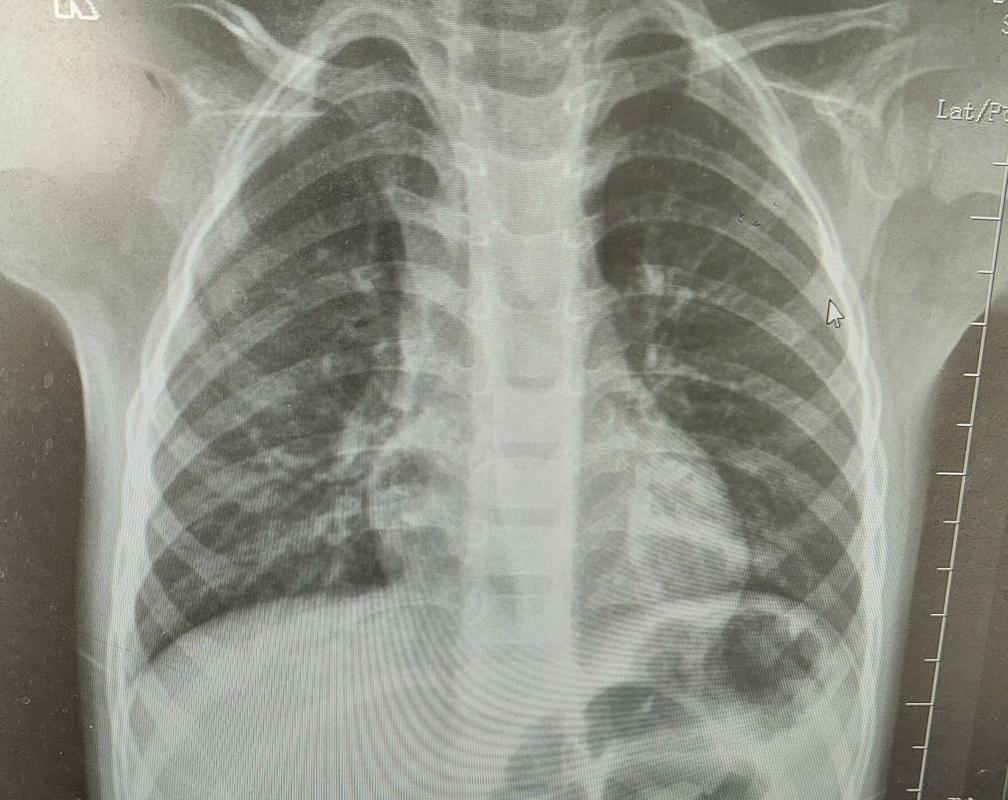

CT(计算机断层扫描)能够提供非常清晰、详细的肺部影像,这是其他检查(如X光)难以比拟的,对于新生儿,尤其是在以下情况,CT是至关重要的诊断工具:

- X光无法明确诊断时: 胸部X光是初步筛查的重要工具,但分辨率有限,当X光结果不典型、无法解释临床症状或需要更精细评估时,CT是“金标准”。